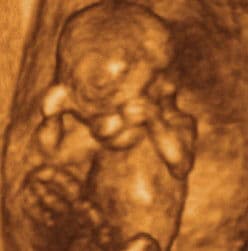

11 weeks and 3 days pregnant

As the baby floats in the amniotic fluid, her limbs are now more fully developed, allowing her to make many movements. The lips and fingers – which are now completely separated – stimulate sensory feelings.